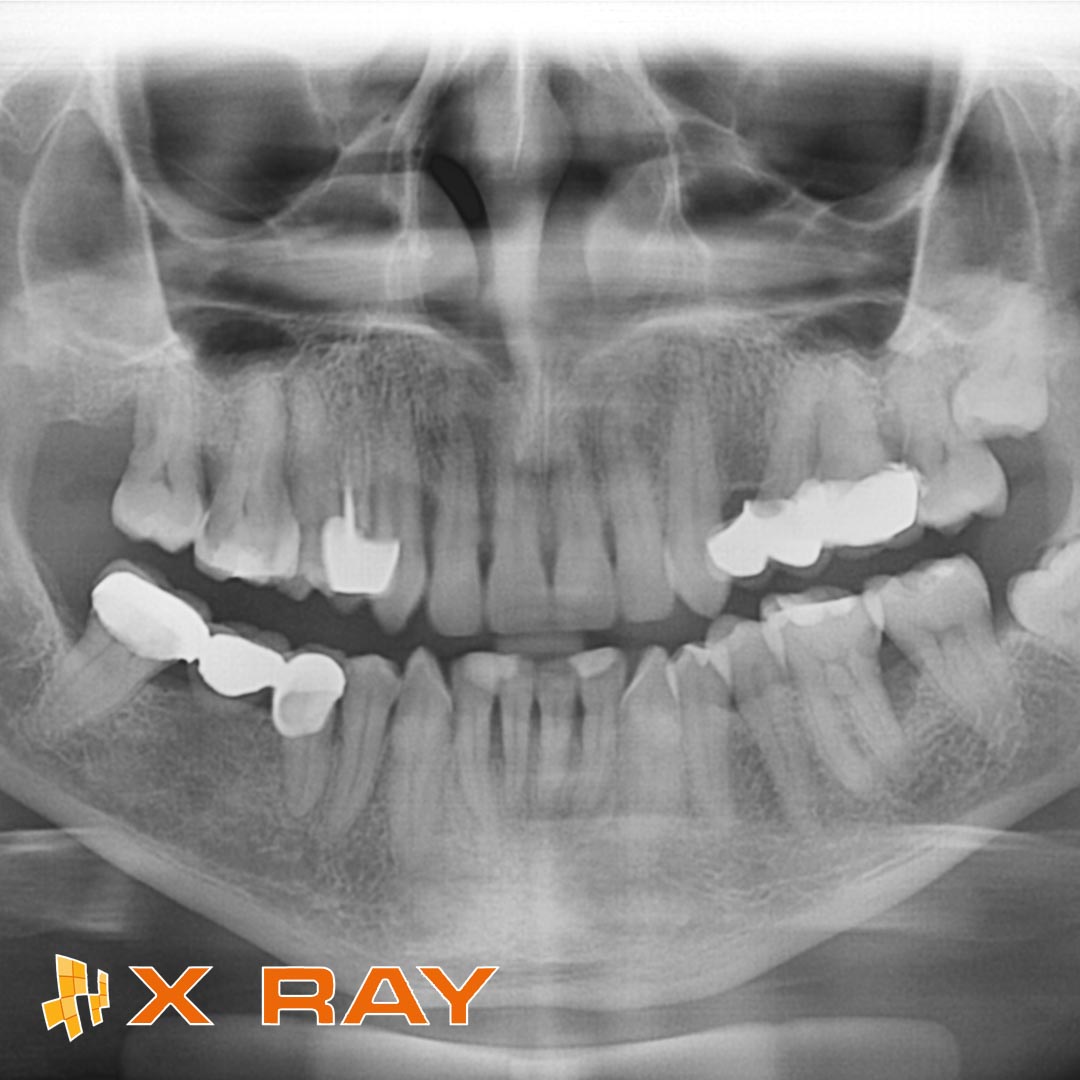

L'ortopanoramica delle arcate dentarie o ortopantomografia

Radiografia atta a visualizzare lo stato di dentizione, le ossa mascellari e le articolazioni temporo-mandibolari.

È l’esame di prima istanza, richiesto per avere una visualizzazione generale dello stato odontoiatrico del paziente e risulta molto utile per indagare eventuali carie, lesioni periapicali e tasche gengivali di relativa importanza.

Grazie all’avvento della tecnologia digitale, è divenuto un esame estremamente poco invasivo con una dose di esposizione pari a circa 3 μSv (dose molto contenuta).

Inoltre grazie ai programmi pediatrici che concentrano ancora maggiormente la zona sensibile, la dose di esposizione è ulteriormente ridotta ad 1 μSv, con grande vantaggio per i nostri piccoli pazienti.